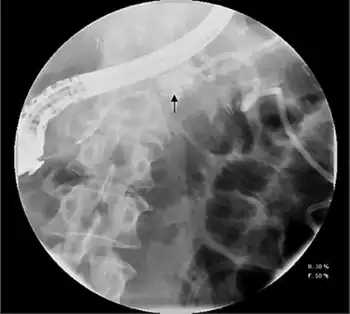

Pancreatogram demonstrating a pancreatic fistula after distal pancreatectomy

Pleural or ascitic fluid should be sent for analysis. An elevated amylase level, usually > 1,000 IU/L, with protein levels over 3.0 g/dL is diagnostic. Serum amylase is often elevated as well, due to enzyme diffusion across the peritoneal or pleural surface.[1][2] Contrast-enhanced computed tomography and endoscopic retrograde cholangiopancreatography (ERCP) may also assist in diagnosis, with the latter an essential component of treatment.